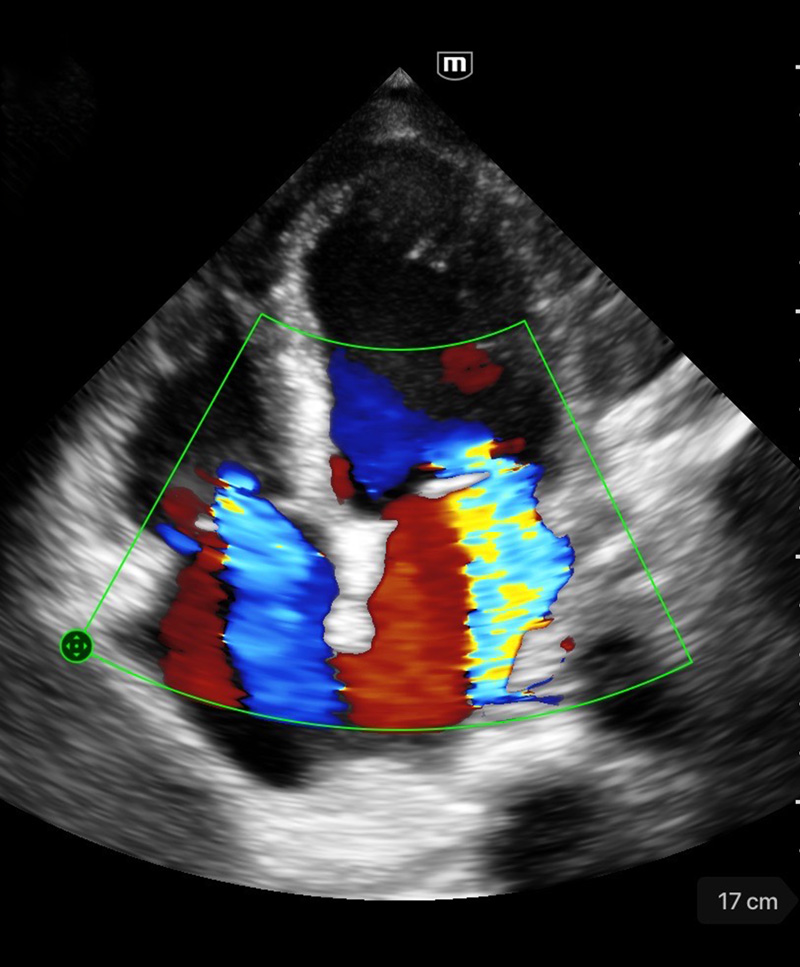

Immagini cliniche

Rigurgito mitrale e tricuspidale

Immagini cliniche

Rigurgito mitrale e tricuspidale